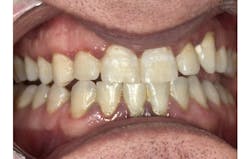

Generalized moderate to severe calculus was present on the lingual surfaces of the mandibular dentition, with black calculus apparent upon activation of the piezo tip when placed subgingivally. The tissue was generally bulbous and dark in color, with severe generalized erythemic tissue and distended tissue in the upper and lower anterior regions.

The patient returned for a four-week follow-up appointment to evaluate whether the tissue had responded well to the soft-tissue treatment. He presented with a total of three sites that bled upon probing. That meant that we saw significant improvement and reduction of bleeding at 137 sites.

When assessing the tissue, the patient presented with tissue that had tightened to the tooth, with only 10 sites remaining over 4 mm. Due to his tissue response and improved home care, we have placed him on a maintenance appointment and will continue to motivate him to achieve meticulous home care.

Not only did we achieve the desired tissue result, but the patient’s home-care compliance was superior. Additionally, he had reported increased gingival comfort when brushing and flossing. The patient noted that the treatment was “the most detailed and thorough hygiene visit I have ever had, without any pain.”